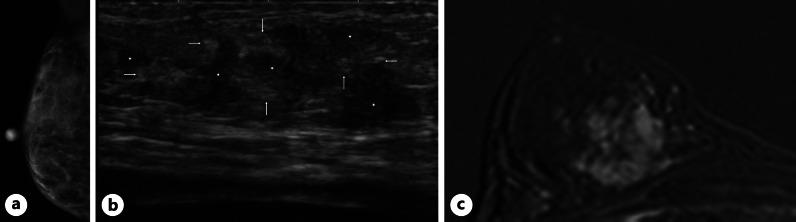

A 54-year-old woman with pseudomyxoma peritonei from an appendiceal signet ring cell carcinoma was referred to our hospital. Right massive effusion with cytology-proven malignant cells was controlled with thoracentesis. Pathological study after intraperitoneal (IP) chemotherapy, hyperthermic IP chemotherapy, and cytoreductive surgery showed no malignant cells in the abdomen except for the appendix and greater omentum. Although the patient noticed a right breast mass, mammography (MMG) showed no abnormality. Ultrasonography showed right breast masses consisting of hypo- and hyper-echoic areas without clear tumor margins. Magnetic resonance imaging (MRI) with contrast medium showed multiple lesions showing persistent enhancement pattern. Pathological study of the vacuum-assisted biopsy specimen showed signet ring cells growing in diffuse, trabecular, and linear fashions, leading to the diagnosis of metastatic breast tumors from the appendiceal signet ring cell carcinoma. Positron emission tomography (PET)/computed tomography (CT) showed no fluorodeoxyglucose uptake in the breasts. The patient was treated with simple mastectomy for local control. Pathological study of the resected breast showed predominant localization of the metastatic breast tumors deep in the mammary gland and lymphovascular invasion. Metastatic breast tumors from appendiceal signet ring cell carcinomas are extremely rare and can sometimes be difficult to detect with MMG and PET/CT. General surgeon should note that appendiceal signet ring cell carcinomas can metastasize to the breast, presumably through lymphatic permeation from malignant pleural effusion, without abnormal MMG and PET/CT findings.

一名54岁患有阑尾印戒细胞癌所致腹膜假黏液瘤的女性被转诊至我院。经胸腔穿刺术控制了右侧大量伴有细胞学证实恶性细胞的胸腔积液。腹腔内(IP)化疗、热灌注IP化疗及肿瘤细胞减灭术后的病理研究显示,除阑尾和大网膜外,腹部未见恶性细胞。尽管患者发现右侧乳腺有肿块,但乳腺X线摄影(MMG)未显示异常。超声检查显示右侧乳腺肿块由低回声和高回声区域组成,边界不清。增强磁共振成像(MRI)显示多个病灶呈持续强化模式。真空辅助活检标本的病理研究显示印戒细胞呈弥漫、小梁状和线状生长,从而诊断为阑尾印戒细胞癌转移至乳腺。正电子发射断层扫描(PET)/计算机断层扫描(CT)显示乳腺无氟脱氧葡萄糖摄取。患者接受了单纯乳房切除术以控制局部病情。切除乳腺的病理研究显示,转移性乳腺肿瘤主要位于乳腺深部并伴有淋巴管浸润。阑尾印戒细胞癌转移至乳腺极为罕见,有时MMG和PET/CT难以检测到。普通外科医生应注意,阑尾印戒细胞癌可转移至乳腺,推测是通过恶性胸腔积液的淋巴渗透,而MMG和PET/CT检查无异常发现。